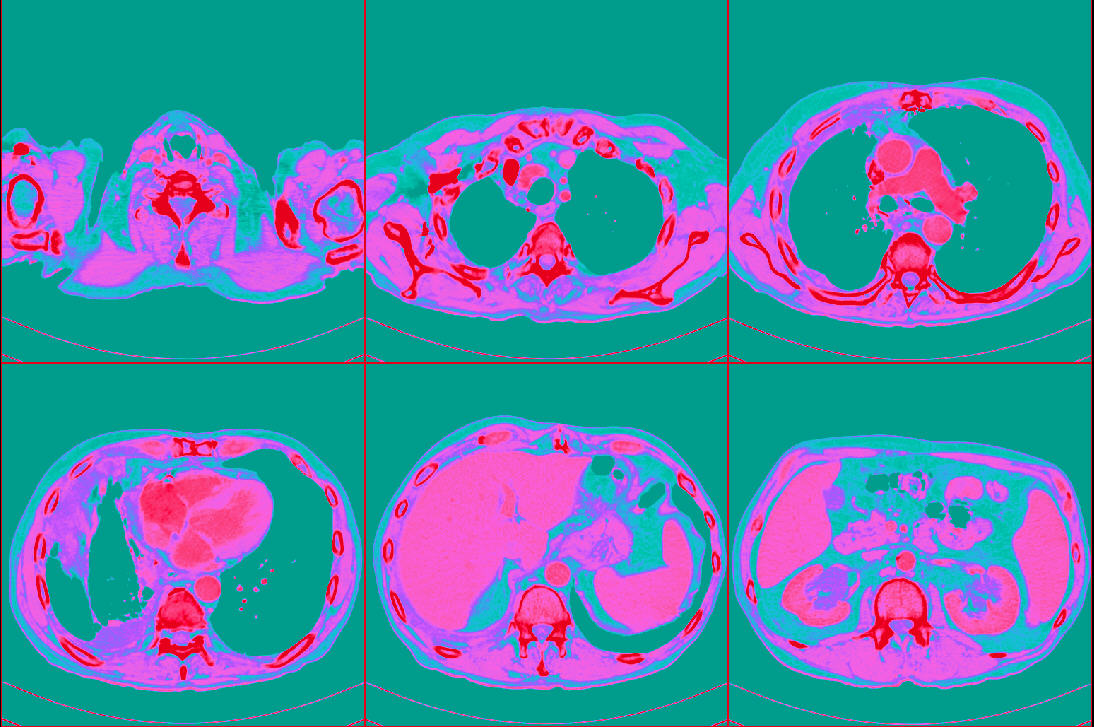

The Cancer Genome Atlas Lung Adenocarcinoma (TCGA-LUAD) 是一个肺癌CT影像数据,源自另一个更大的癌症数据项目 The Cancer Genome Atlas (TCGA),旨在对各种类型的癌症诊治过程进行全程数字化的跟踪,以数字档案的形式记录检查结果、处方和疗效。

| 数据介绍: | The Cancer Genome Atlas Lung Adenocarcinoma (TCGA-LUAD) 是一个肺癌CT影像数据,源自另一个更大的癌症数据项目 The Cancer Genome Atlas (TCGA),旨在对各种类型的癌症诊治过程进行全程数字化的跟踪,以数字档案的形式记录检查结果、处方和疗效。 |